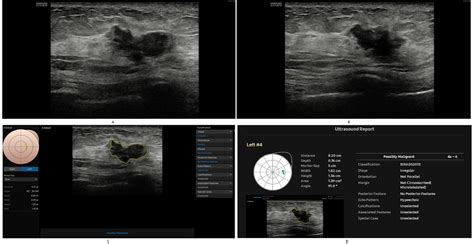

Computer Aided Diagnosis systems function by processing complex medical data through sophisticated computational models. Whether it is an X-ray, a CT scan, an MRI, or a pathology slide, the software analyzes the data to detect patterns, textures, and structures that are characteristic of specific diseases or conditions. The process generally involves several stages:

• Image Pre-processing: Cleaning up noise and improving image quality for better analysis.

• Segmentation: Isolating specific anatomical regions or lesions from the background tissue.

• Feature Extraction: Identifying quantitative markers such as shape, density, size, and intensity.

• Classification: Using machine learning to label the findings as benign or malignant, or identifying specific pathologies.

• Radiology: Used extensively for mammography to detect microcalcifications and for lung cancer screening through chest CT scans.

• Computer Aided Diagnosis Ultrasound